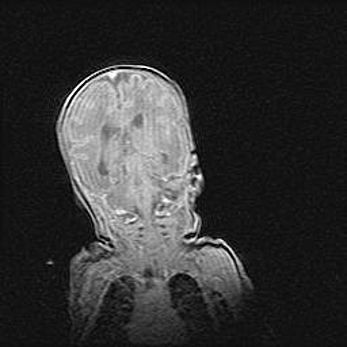

Наружная гидроцефалия с возможной атрофией височных областей.

Возраст: 28 дней

Вес: 3670 г

Пол: мужской

Окружность головы: 38 см

Срок гестации: 40 недель

Гидроцефалия головного мозга у новорожденных – это заболевание, которое характеризуется скоплением избыточного количества спинномозговой жидкости в желудочковой системе головного мозга в результате затруднения её перемещения от места выработки к месту поглощения в кровеносную систему или вследствие нарушения абсорбции. При открытой наружной форме гидроцефалии у новорожденных расширяются и переполняются субарахноидные пространства.

При нормотензивных  формах,  которые,  как  правило,  являются  следствием  перенесенных ишемических  повреждений  паренхимы  мозга,  возможно  сочетание микроцефалии  с нормотензивной гидроцефалией. В основе данных изменений лежит атрофия больших полушарий с преимущественной  локализацией  в  лобно-височных  областях.